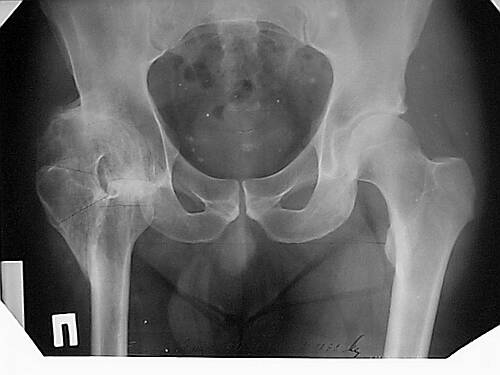

Уважаемые коллеги!Женщина, 35 летВ прошлом по поводу врожденного вывиха бедра перенесла операцию остеотомии по Шанцу

с удлинением правой ноги за счет бедра на уровне диафиза. В последнее время прогрессируют боли в правом тазобедренном суставе, порочное положение правой ноги, затруднена ходьба.Вопросы:1) Целесообразно ли эндопротезирование правого тазобедренного сустава?2) Целесообразный ли следующие действия: канал бедренной кости предполагаем вскрыть для введения ножки протеза на высоте угловой деформации, предполагаем низведение большого вертела с мышцами; протез будет подобран индивидуально, предполагается умеренная версия?В приложении рентгенограммы и трехмерная КТ.В цветном и более качественном варианте КТ размещена здесь